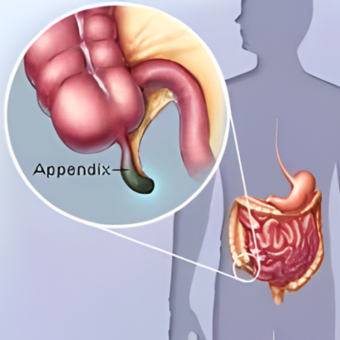

Appendicitis

02. Laparoscopic Appendectomy

Safe, minimally invasive removal of an inflamed appendix reducing complications and healing time.